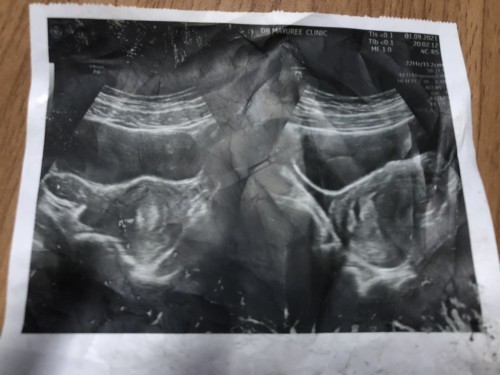

ตามหัวข้อเลยคะแม่ ๆ เจอน้องตอนกี่วีคคะ วันนี้ไปหาคุณหมอมา ไม่เจออะไรเลยคะ คุณหมอบอกว่าเปนไปได้ 2 อย่าง 1 ท้องนอกมดลูก 2 อายุครรภ์ยังน้อย